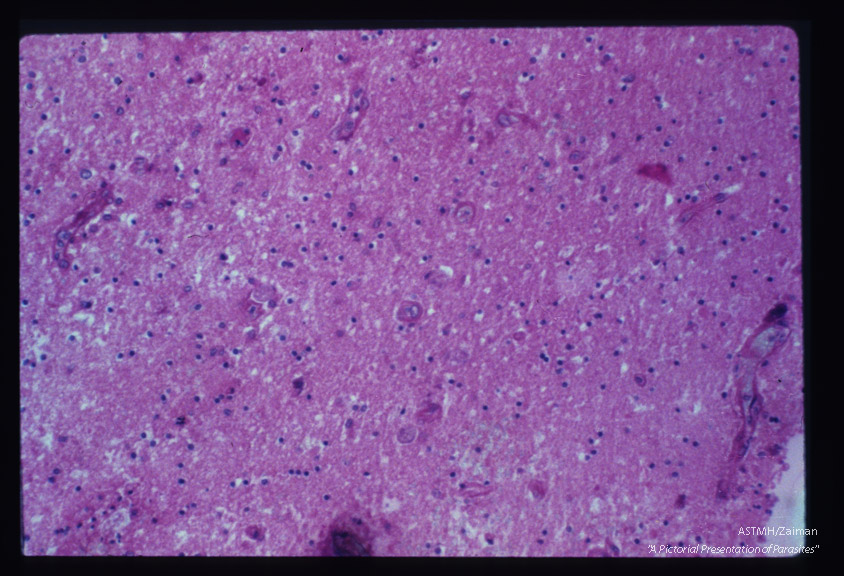

Brain showing glial proliferation and amoeba.

Entamoeba histolytica

Description: Brain showing glial proliferation and amoeba.